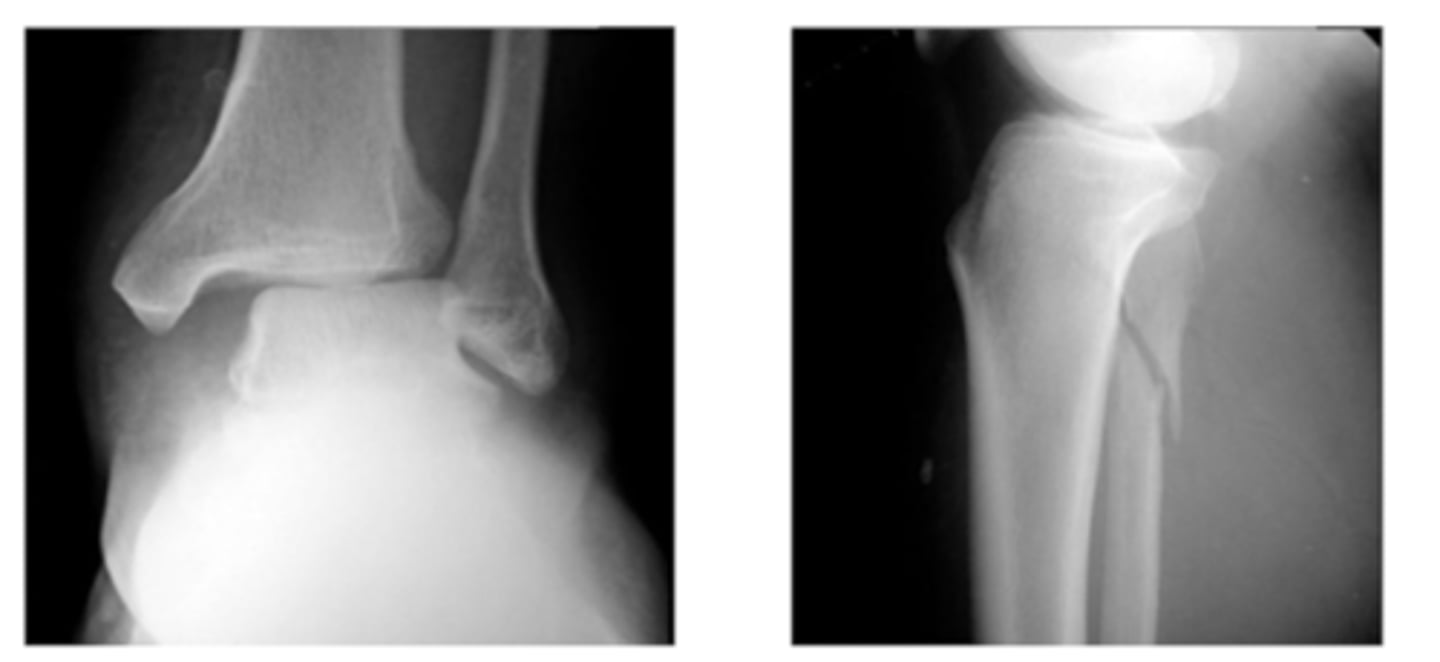

What type of fracture involves the distal tibia and the ankle joint at the tibiotalar articular surface?

pilon fracture

Due to extent of trauma usually associated with a pilon fracture, what type of fracture can also present with it?

fibula fracture